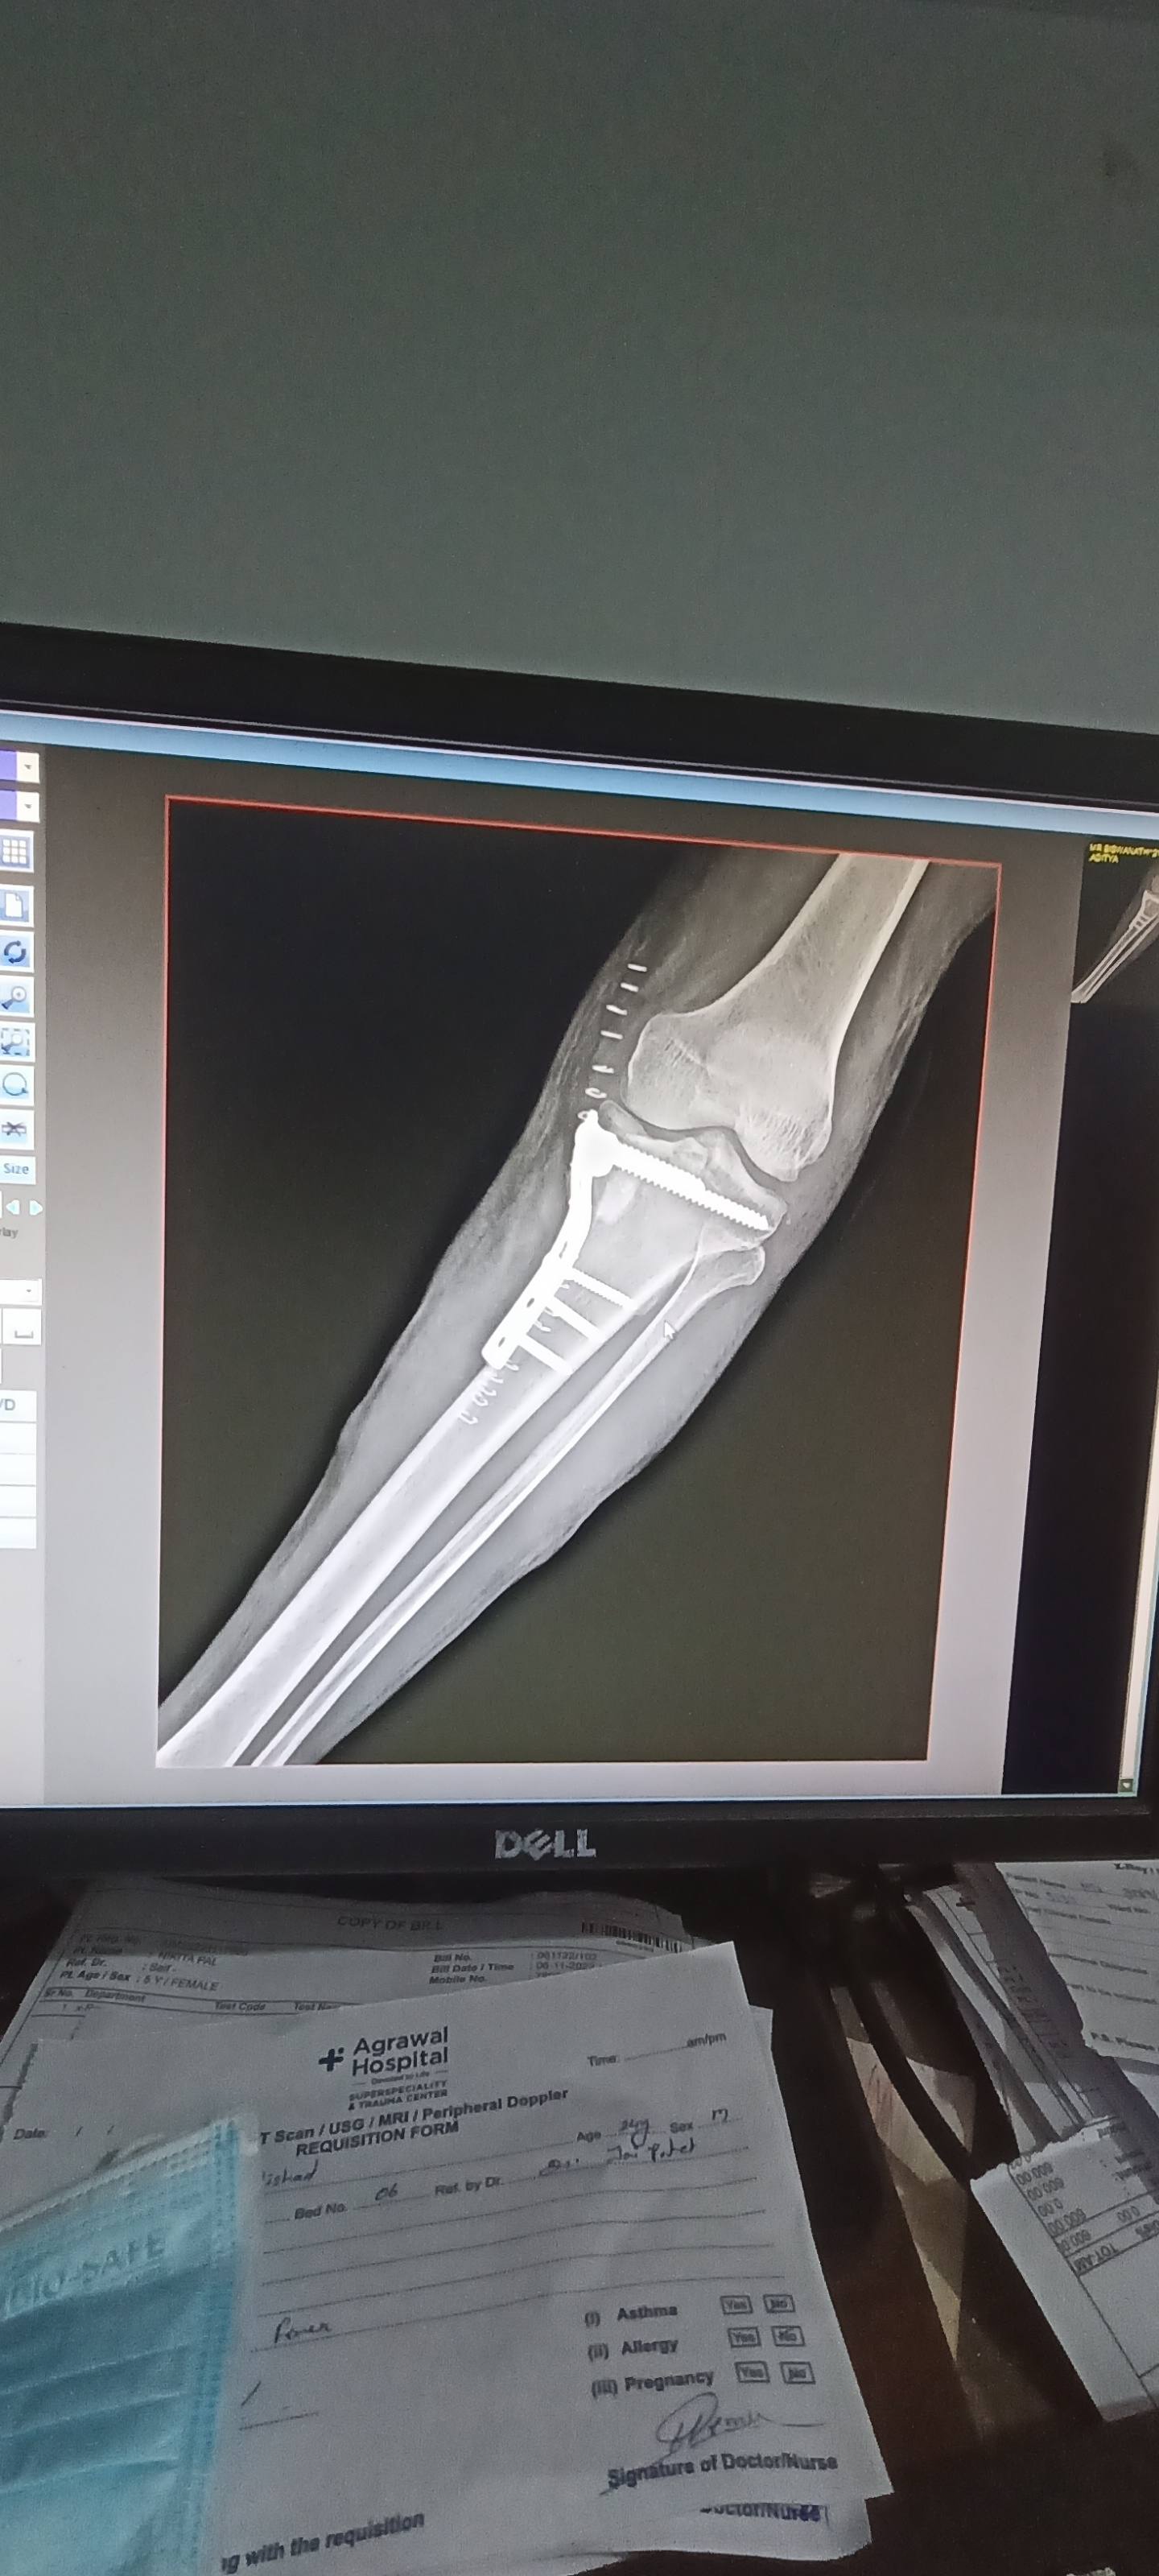

Dear sir mera opretion hue 1 month hochuka he jab me chal ta hun to cut cut jesi sound ata he or thai b thotha patli padgehihe sir ligament ya meniscus tear ka problem to Nehi he please help me sir